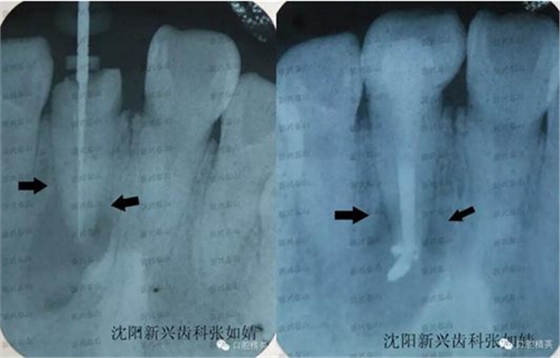

戴牙后拍了一張X線片,根管治療一個月了,我想看下他牙根炎癥是否有所好轉(zhuǎn)。

真實的蛻變----熱牙膠根管充填之后的牙冠修復(fù)真實的蛻變----熱牙膠根管充填之后的牙冠修復(fù),左圖為治療時確定牙根長度是否準(zhǔn)確時拍的X線片,右圖為戴牙之后X線影像,右圖牙齒有些拉長了。

兩圖對比,注意箭頭指向處距根尖的位置,治療后炎癥區(qū)域,即根尖的大面積陰影,有好轉(zhuǎn)的跡象,陰影的邊緣開始向根尖縮聚。由于炎癥太重,根尖此處的病灶要慢慢吸收,是一個過程,治療一個月時間,已好轉(zhuǎn)很多,長期追蹤這個患者的病情,定期復(fù)診,觀察病灶區(qū)域的變化,及時掌握牙齒情況。

從右圖顯而易見的,牙冠修復(fù)體的透光度和鄰牙非常接近,沒有形成低密度阻射的影像。